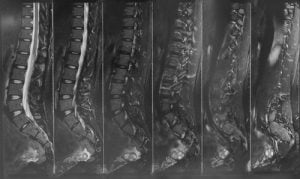

Figure showing Xray & MRI plate. A digital xray gives a proper image of the spine , while the MRI gives a detailed picture of the Spine with nerves and the spinal cord visualised clearly

- An MRI scan is the basic investigation required for diagnosis of a spinal problem as it shows the neural elements like the disc, the nerves and the spinal cord very well. A 1.5 T MRI scan is the minimum required scan nowadays, while some patients are claustrophobic and may find it difficult to go through the scan, for them the scan can be done under sedation, that is we give an injection so that patients can sleep through the procedure.